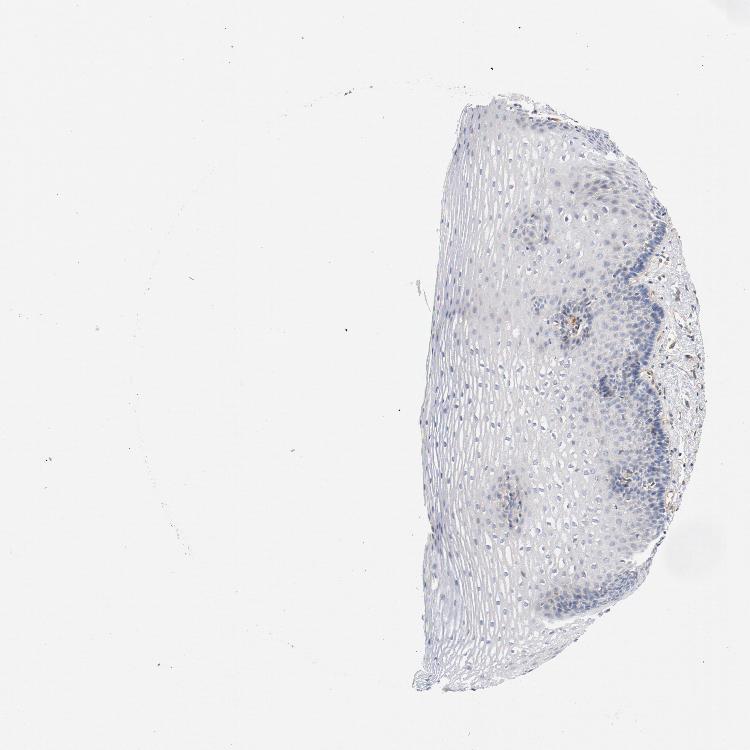

ESOPHAGUS - Antibody stainingi

Antibody staining in the annotated cell types in the current human tissue is reported as not detected, low, medium, or high, based on conventional immunohistochemistry profiling in selected tissues. This score is based on the combination of the staining intensity and fraction of stained cells.

Each image is clickable and will lead to virtual microscopy that enables deeper exploration of all samples and also displays staining intensity scores, fraction scores and subcellular localization as well as patient and tissue information for each sample.

Antibody CAB004041

Squamous epithelial cells Not detected